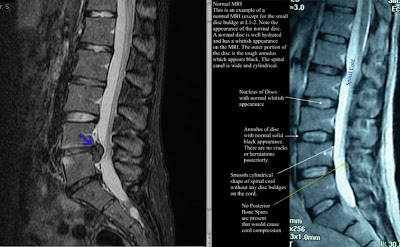

It's been exactly 2 weeks since I had back surgery for an L4/5 disc herniation. And I think it's now ok to say that it's probably working.

After feeling that I missed out on making the most of surfing on Waikiki due to back pain (I didn't take any opioids b/c I didn't think it'd be wise to swim 'high'), I finally saw a spine based ortho in November. He is a mellow guy, not a rainmaker surgeon, as he's booked well into 2009. So I was taken aback at the words spoken upon his review of the MRI: "you're probably going to come begging for surgery w/in the next few months". After several days of contemplation and a surprisingly nerve-wracking epidural steroid injection that yielded zero relief, surgery was booked.

I keep anticipating pain & still find myself bracing for pain before sneezing or coughing but I'm sure that sort of gating behavior will fade with time. Only the offending piece of disc was removed and that the remaining disc was left alone. Prior to surgery I asked if there was any way to sure up the remaining disc to prevent further reherniation. The ortho replied that he has not seen any difference in outcomes for discs left treated or untreated prioir to closure. In general, discectomies are more successful for relieving leg numbness/pain and less so for back pain. I was told there's a reasonable chance for more back surgery (disc replacement) in the *distant* future. Time will tell. Sooo thankful for decent health insurance.